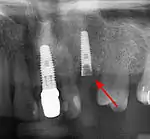

Long term

The long-term complications that result from restoring teeth with implants relate directly to the risk factors of the patient and the technology. There are the risks associated with appearance including a high smile line, poor gingival quality and missing papillae, difficulty in matching the form of natural teeth that may have unequal points of contact or uncommon shapes, bone that is missing, atrophied or otherwise shaped in an unsuitable manner, unrealistic expectations of the patient or poor oral hygiene. The risks can be related to biomechanical factors, where the geometry of the implants does not support the teeth in the same way the natural teeth did such as when there are cantilevered extensions, fewer implants than roots or teeth that are longer than the implants that support them (a poor crown-to-root ratio). Similarly, grinding of the teeth, lack of bone or low diameter implants increase the biomechanical risk.[74] : 27–51 Finally there are technological risks, where the implants themselves can fail due to fracture or a loss of retention to the teeth they are intended to support.[74]: 27–51

Long-term failures are due to either loss of bone around the tooth and/or gingiva due to peri-implantitis or a mechanical failure of the implant. Because there is no dental enamel on an implant, it does not fail due to cavities like natural teeth. While large-scale, long-term studies are scarce, several systematic reviews estimate the long-term (five to ten years) survival of dental implants at 93–98 percent depending on their clinical use.[2][3][4] During initial development of implant retained teeth, all crowns were attached to the teeth with screws, but more recent advancements have allowed placement of crowns on the abutments with dental cement (akin to placing a crown on a tooth). This has created the potential for cement, that escapes from under the crown during cementation to get caught in the gingiva and create a peri-implantitis (see picture below). While the complication can occur, there does not appear to be any additional peri-implantitis in cement-retained crowns compared to screw-retained crowns overall.[75] In compound implants (two stage implants), between the actual implant and the superstructure (abutment) are gaps and cavities into which bacteria can penetrate from the oral cavity. Later these bacteria will return into the adjacent tissue and can cause periimplantitis.

Criteria for the success of the implant supported dental prosthetic varies from study to study, but can be broadly classified into failures due to the implant, soft tissues or prosthetic components or a lack of satisfaction on the part of the patient. The most commonly cited criteria for success are function of at least five years in the absence of pain, mobility, radiographic lucency and peri-implant bone loss of greater than 1.5 mm on the implant, the lack of suppuration or bleeding in the soft tissues and occurrence of technical complications/prosthetic maintenance, adequate function, and esthetics in the prosthetic. In addition, the patient should ideally be free of pain, paraesthesia, able to chew and taste and be pleased with the esthetics.[72]